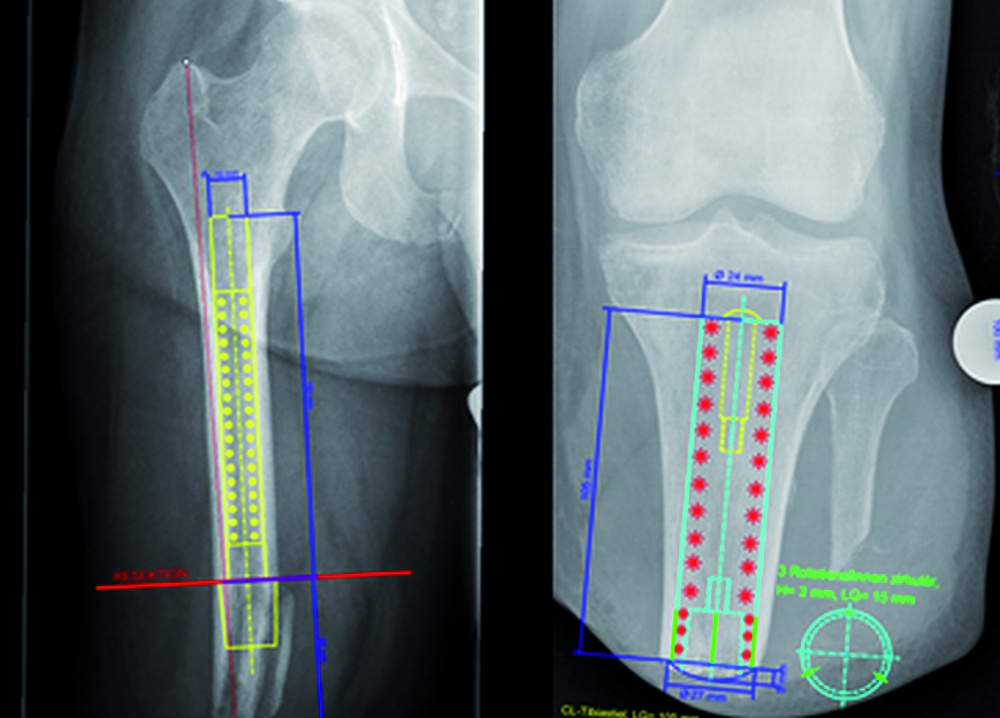

Die Röntgenaufnahmen des residualen Femur zeigte eine leicht dehiszent stehende Knochenlamelle am distalen Ende des -Knochens bei sonst unauffälligem Restknochenrohr; mit 115 mm war der Tibiastumpf ausreichend lang zur Aufnahme eines individuell anzufertigenden Implantates. In einer CT-Untersuchung des Beckens zeigten sich die Frakturen des Os sacrum knöchern vollständig konsolidiert, lediglich die Fraktur des Ramus ossis pubis inferior dexter war pseudarthrotisch geblieben; hieraus ergab sich jedoch keine Kontraindikation hinsichtlich der geplanten Implantation (Abbildung 4).

Nach individueller Fertigung der Implantate erfolgte im April 2016 in einem ersten Operationsschritt die Implantation der sogenannten „Endomodule“ in den rechten Femur- sowie den linken Tibiastumpf. Der Femurstumpf wurde dabei unter Entfernung der dehiszenten Knochenlamelle um 5,5 cm gekürzt. Der postoperative Verlauf wurde durch eine Pneumonie und eine passagere Blutungsanämie erschwert; wegen vermehrter Blutung aus den Redondrainagen des rechten Oberschenkelstumpfes musste am Abend des Operationstages eine Revision mit Hämatomausräumung erfolgen. Nach dreitägiger intensivmedizinischer Betreuung erholte sich der Patient dann rasch, die Wundheilung verlief per primam, die postoperativen Röntgenkontrollen zeigten die regelhafte Lage der Implantate (Abbildung 6a). Ein bereits bei der Aufnahme bei uns bestehendes ausgeprägtes chronisches Schmerzsyndrom erforderte über den gesamten stationären Aufenthalt eine intensive Betreuung durch den Schmerztherapeuten.